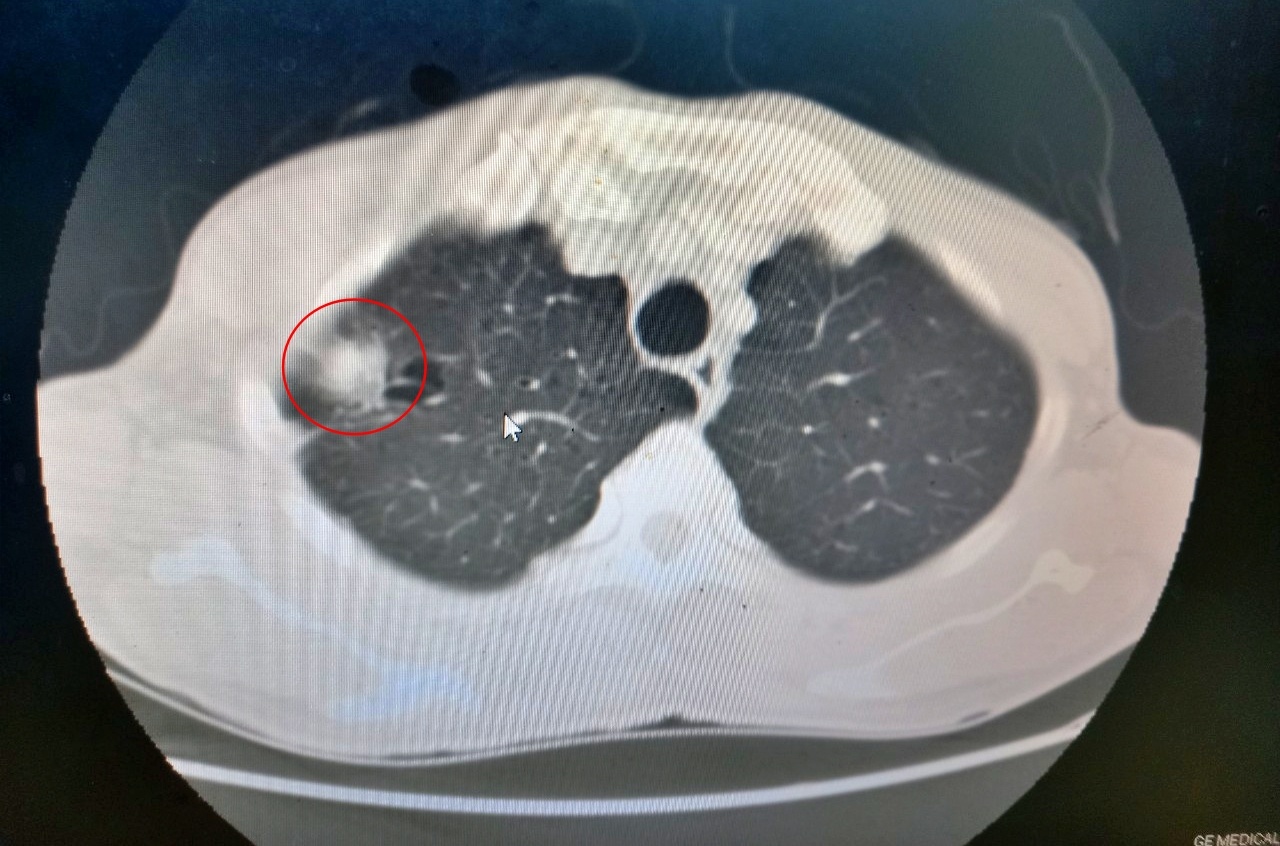

Qua thăm khám, chụp cắt lớp vi tính, bác sĩ phát hiện khối u thùy trên phổi phải. Kết quả sinh thiết xác định đây là khối u ác tính. Các bác sĩ chẩn đoán bệnh nhân bị ung thư phổi phải.

Qua đường rạch 3 cm tại khoang liên sườn ở thành ngực, phẫu thuật viên đưa camera và dụng cụ phẫu thuật kiểm tra. Trên máy nội soi, khối u thùy trên phổi phải kích thước 2x2 cm, mật độ chắc, ranh giới rõ, trong có nhiều ổ hoại tử nhỏ gây co kéo màng phổi, xâm lấn dính thành ngực nhẹ, xung quanh có hạch mềm.

Khối u ác tính phổi phải của bệnh nhân H. trên phim chụp cắt lớp vi tính. Ảnh: BVCC.